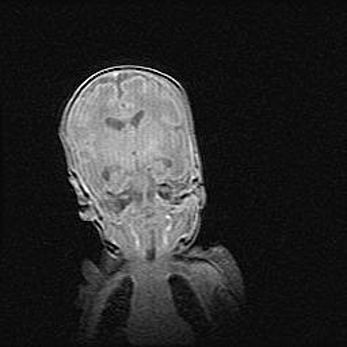

Сообщающаяся гидроцефалия. Кистозная энцефаломаляция головного мозга.

Возраст: 3 месяца 4 дня

Вес: 3100 г

Пол: женский

Окружность головы: 34 см

Срок гестации: 31 неделя

Кистозная энцефаломаляция головного мозга - одна из форм поражения головного мозга в детском возрасте. Характеризуется возникновением множественных и распространённых кист в коре, белом веществе и подкорковых образованиях головного мозга у плодов, новорождённых и детей раннего возраста. Развитие кистозной энцефаломаляции связано с внутриутробной асфиксией и гипотонией, родовой травмой, тромбозом синусов, пороками развития сосудов, инфекциями, сепсисом и другими причинами. Наиболее значимые инфекционные агенты: вирусы простого герпеса, цитомегалии, краснухи, токсоплазмы, энтеробактерии, золотистый стафилококк и другие.